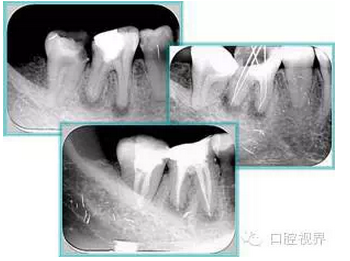

7. 器械折斷

右圖及下圖為器械折斷的 X 線片。箭頭處示折斷器械。

二、臺階

右圖箭頭處示臺階形成。